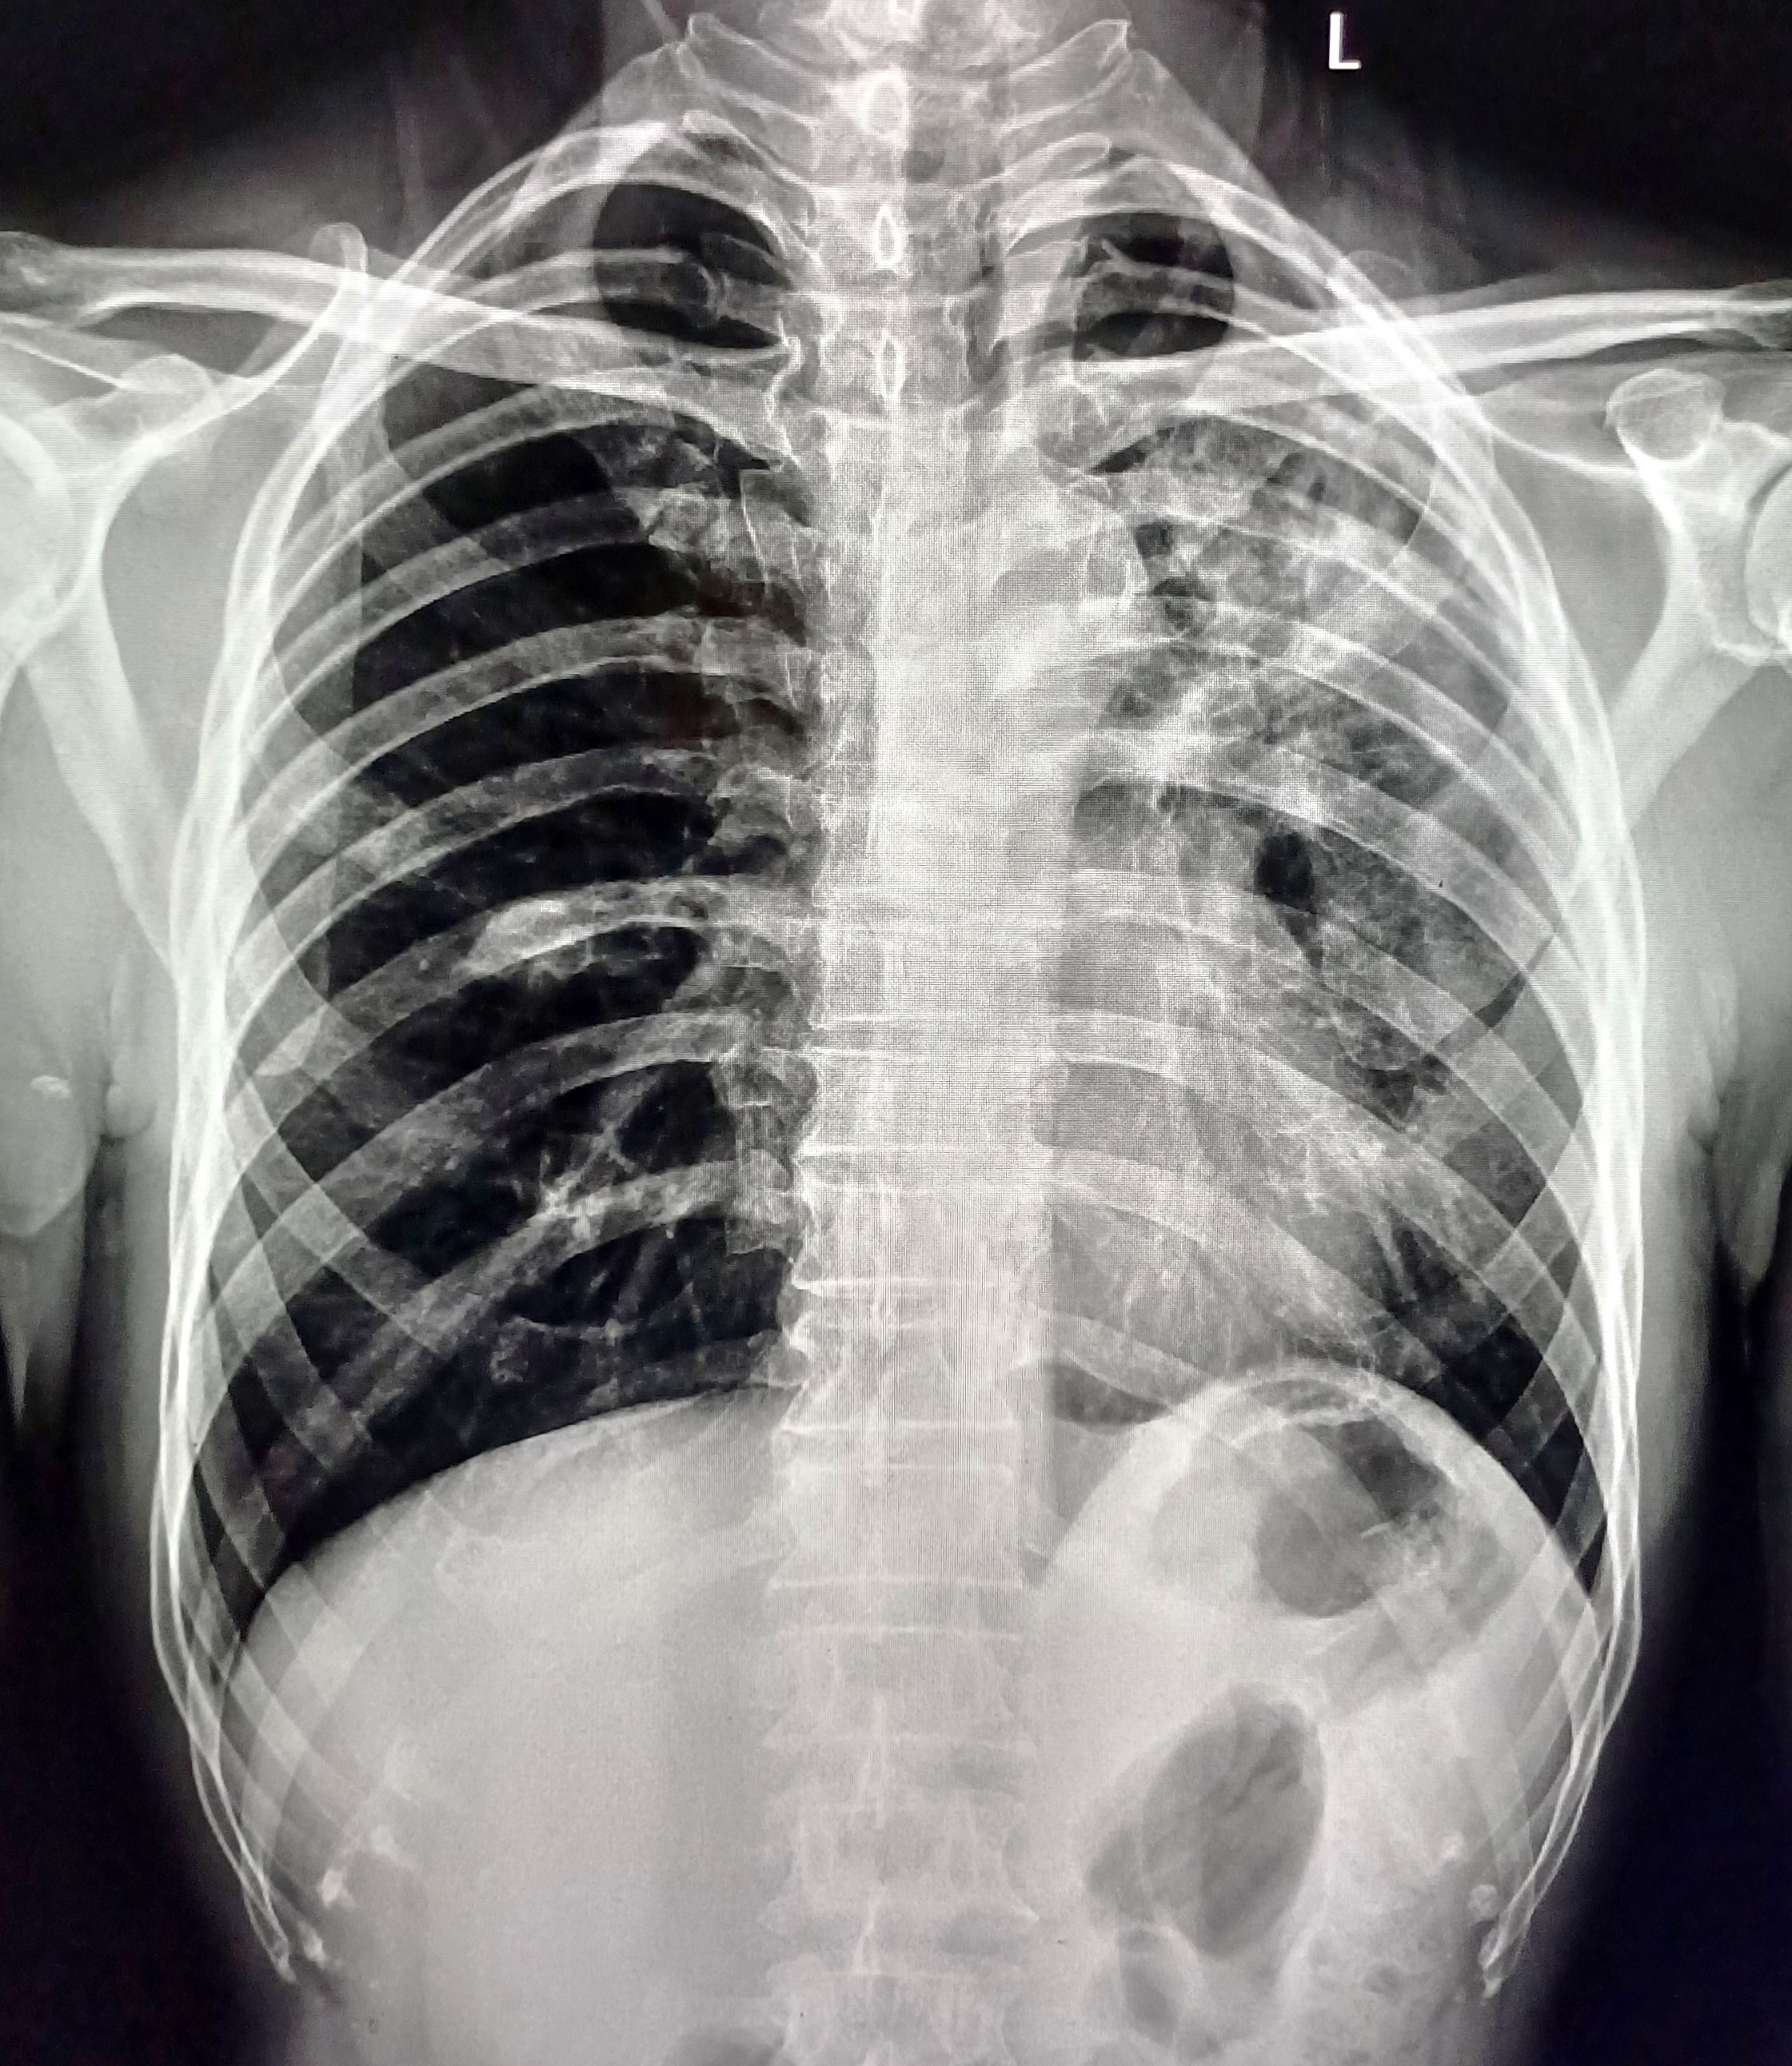

| 5 | IGGMC, Nagpur, Nagpur | P2 | 29-4467 | Meera Gohare | Consent taken on Paper | 64 Yrs. |

Provisional Diag : ?

Final Diag : Disseminated TB (Miliary TB With Abdomen Koch) |

TB Case (Confirmed) | Abnormality visible on x-ray |

View |